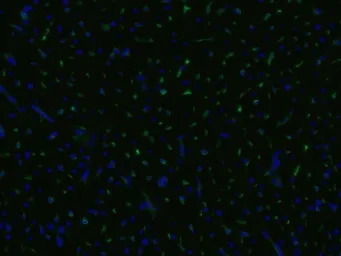

Immunofluorescence staining of an infarcted porcine heart with anti-CD105 (MEM-229; green; GTX79974); cell nuclei stained with DAPI (blue).